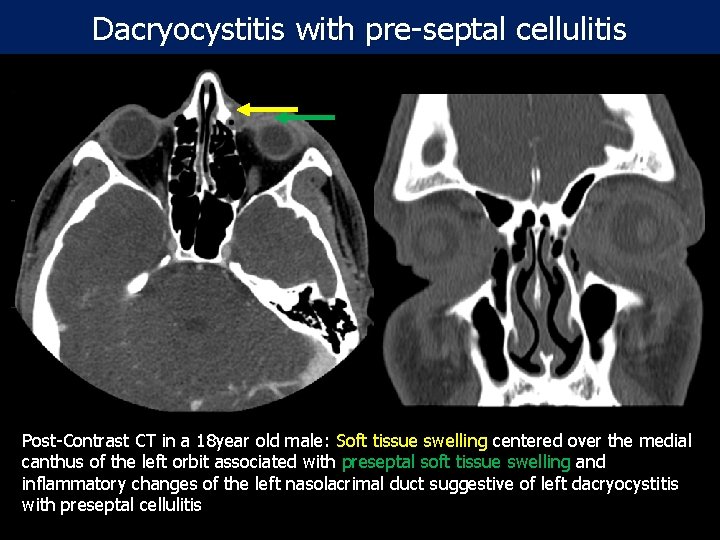

Dacryocystitis with pre-septal cellulitis Post-Contrast CT in a 18 year old male: Soft tissue swelling centered over the medial canthus of the left orbit associated with preseptal soft tissue swelling and inflammatory changes of the left nasolacrimal duct suggestive of left dacryocystitis with preseptal cellulitis